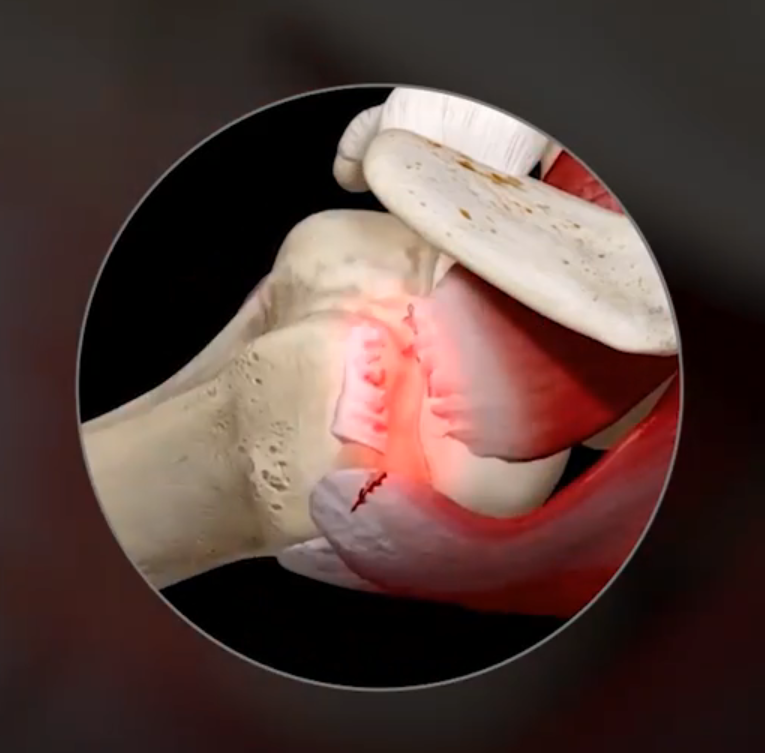

- Ruptura do Manguito Rotador – Essa lesão pode ser parcial ou completa e, geralmente, resulta de trauma agudo (como uma queda) ou do desgaste progressivo ao longo dos anos. As rupturas completas podem exigir intervenção cirúrgica para reparo.

7. Como é a cirurgia?

A cirurgia é feita por artroscopia (mínima invasão). Passo a passo:-

- Limpeza do tecido doente]

- Preparação da área do osso

- Colocação de âncoras

- Sutura dos tendões rompidos

- Reparo anatômico da lesão

8. O que é uma âncora no ombro?

Muitos pacientes perguntam isso.

Âncora é um pequeno dispositivo (geralmente de titânio ou material absorvível) usado para fixar o tendão de volta ao osso.

Ela funciona assim:

- uma parte vai presa ao osso

- fios saem da âncora

- esses fios costuram o tendão

- o tendão é reinserido na posição correta